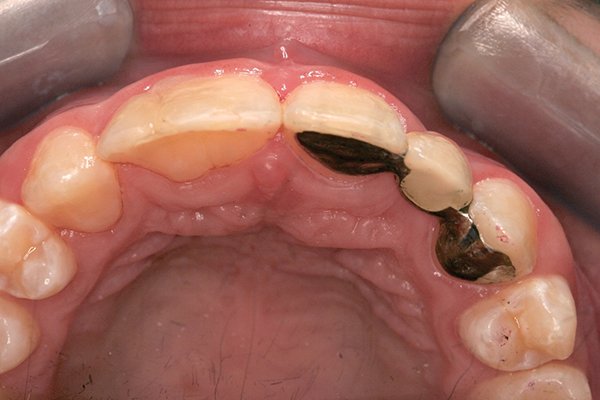

Fig 3. Radiographic scan of fused maxillary central-peg lateral incisors, teeth Nos. 7 and 8, and congenitally missing lateral incisor, tooth No. 10.

Figure 3

A 9-year-old girl, referred to a prosthodontic office by her pediatric dentist, presented with her mother’s chief complaint: “The kids are teasing her about her big front tooth.” Findings from radiographic and clinical examinations revealed fused maxillary central-peg lateral incisors, teeth Nos. 7 and 8, and a congenitally missing lateral incisor, tooth No. 10 (Figure 1 through Figure 3). An implant was selected as the ideal treatment to replace tooth No. 10 when somatic growth was complete. A diagnostic wax-up was fabricated to determine if the fused tooth could be made to resemble two teeth, using pink composite to give the illusion of an interproximal papilla. The patient was referred for an orthodontic consultation to plan for closure of the diastema between teeth Nos. 8 and 9 and achievement of proper alignment for implant No. 10. The patient was also referred to a periodontist for pretreatment assessment of the tooth No. 10 site. An endodontist was consulted should exposure of the large pulp occur during tooth preparation.